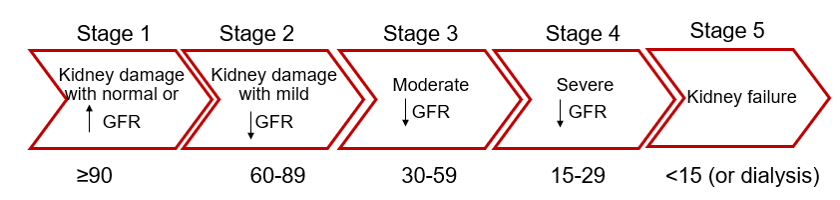

Nephropathy

Depending on the Glomerular Filtration Rate (expressed in ml/min/1,73m2), we can distinguish 5 stages for the kidney function condition. For children and elderly patients, the clearance is low therefore it is very important to perform an analysis on a blood sample before injecting any contrast agent.